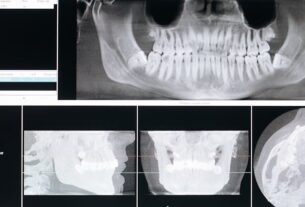

Leczenie w jeden dzień to model terapii, w którym diagnoza, plan leczenia oraz wykonanie właściwego zabiegu odbywają się podczas jednej wizyty lub w ciągu jednego dnia. Jest to możliwe dzięki zastosowaniu zaawansowanych technologii cyfrowych, takich jak skanery wewnątrzustne, tomografia komputerowa CBCT czy systemy CAD/CAM do projektowania i frezowania uzupełnień protetycznych.

Warunkiem powodzenia takiego leczenia jest odpowiednia ilość i jakość tkanki kostnej oraz brak aktywnego stanu zapalnego. Nowoczesna diagnostyka obrazowa pozwala precyzyjnie zaplanować zabieg i zminimalizować ryzyko powikłań.